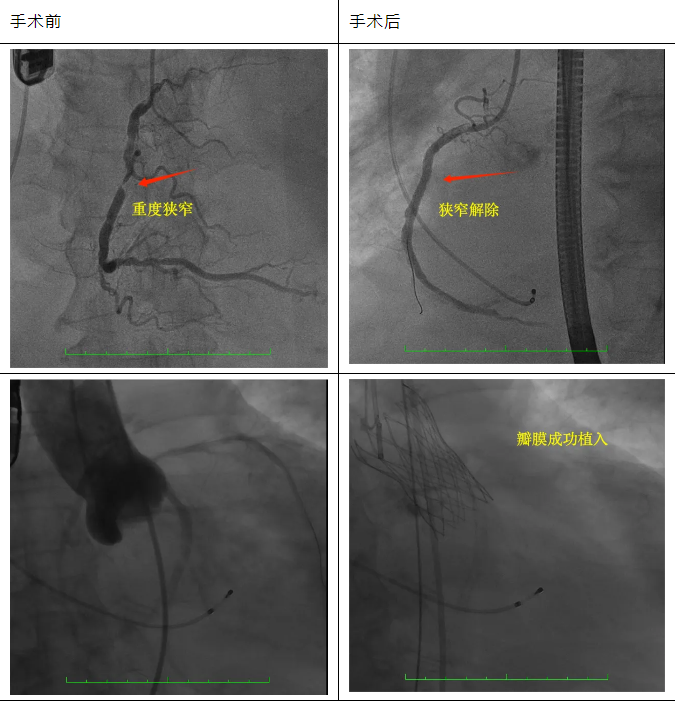

此患者是家住茂南的梁叔,他因胸痛、胸闷、气促紧急到茂名市人民医院急诊就诊。超声检查提示:主动脉瓣退行性变;主动脉瓣狭窄(重度),并关闭不全(中度),左心、右房增大。EF31%(正常为:50%~75%)。因其有冠心病史,医护人员遂将梁叔送入心血管内科一区接受进一步治疗。CTA检查显示,梁叔主动脉瓣二叶畸形合并重度狭窄,极重度钙化,冠脉造影显示右冠脉严重狭窄。

心血管内科医护团队联合心内CCU、心外科、导管介入室、麻醉手术室、超声诊断科等多学科为患者实施手术。从穿刺颈内静脉行临时起搏器植入,到植入支架,再到主动脉瓣植入,从导丝跨瓣、球囊扩张到瓣膜植入,每一步都有条不紊,最后精准释放瓣膜装置,成功完成PCI+TAVR手术。术后主动脉瓣跨瓣压差明显下降,造影及彩超均证实无瓣周漏,手术过程十分顺利。经过几天的住院休养,目前梁叔已康复出院。